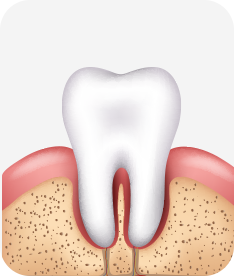

건강한 상태

치아 주위의 잇몸이 핑크색을 띄며, 잇몸에서 피가 나지 않음.

스케일링을 6개월 ~ 1년 주기로 받고 올바른 칫솔질로 건강한 치주 조직을 유지